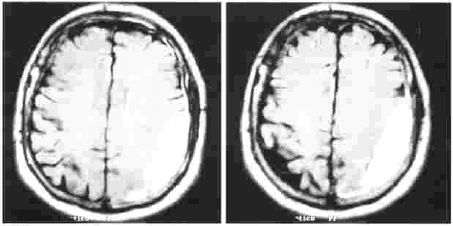

Los controles neurológicos periódicos no muestran signos clínicos de deterioro neurológico, desaparecen totalmente las crisis de paresias en el miembro superior derecho. Las imágenes de resonancia magnética realizada al mes, muestra

Imagen No. 8. Resonancia magnética cerebral a las 4 semanas.

Imagen No. 9. Resonancia magnética cerebral a los 3 meses. Se modificaron las imágenes para eliminar los nombres y los datos del paciente.